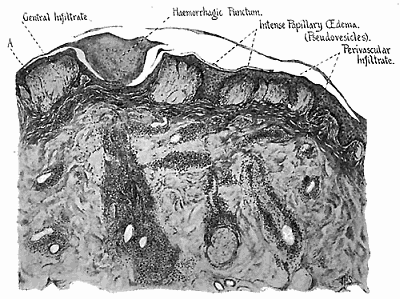

Lesions produced by the bite of the black-fly 321-326

One of the most careful accounts of death from the sting of the scorpion is that of Linnell, (1914), which relates to a comparatively small Malayan species, unfortunately undetermined. The patient, a coolie, aged twenty, was admitted to a hospital after having been stung two days previously on the left heel. For cure, the other coolies had made him eat the head of the scorpion. On admission, the patient complained of "things creeping all over the body". Temp. 102.8°. On the fourth day he had paralysis of the legs, and on the fifth day motor paralysis to the umbilicus, sensation being unaltered. On the sixth day there was retention of the urine and on the ninth day (first test after third day) sugar was present. On the thirteenth day the patient became comatose, but could be roused to eat and drink. The temperature on the following day fell below 95° and the patient was still comatose. Death fifteenth day.

Examination of the spinal (lumbar) cord showed acute disseminated myelitis. In one part there was an acute destruction of the anterior horn and an infiltration of round cells. In another portion[Pg 27] Clarke's column had been destroyed. The perivascular sheaths were crowded with small round cells and the meninges were congested. Some of the cells of the anterior horn were swollen and the nuclei eccentric; chromatolysis had occurred in many of them.